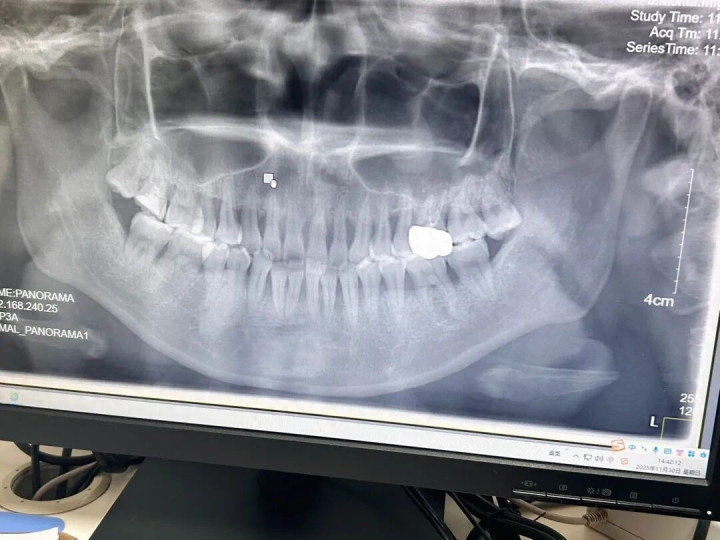

2025年11月,赵玥于武汉市一家三甲牙齿专科病院拍摄的牙片 图/受访者提供